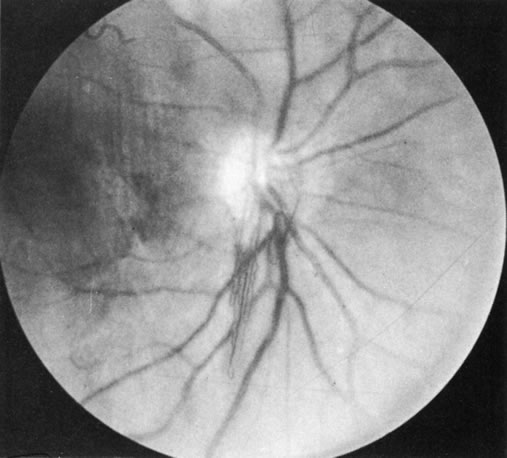

Behçet's disease is a chronic inflammatory disease with widespread clinical manifestations. It affects adults of both sexes, especially in Mediterranean countries and Japan. Classically it consists of a triad of recurrent lesions: iritis, oral ulcers, and genital ulcers (Fig. 6).34 Other common features are vasculitis, skin lesions, optic papillitis (Fig. 7), arthritis, meningomyelitis, and inflammatory bowel disease. Loss of vision is one of its most frequent and serious manifestations. In Japan, the disease is said to be responsible for one-third of all cases of uveitis. Ocular disease occurs in 75% of affected patients, usually in the form of hypopyon, uveitis, occlusive retinal vasculitis, and optic nerve lesions. The cause of Behçet's disease is unknown, but viral, immunologic, and hereditary factors have been suspected.

Fig. 7. Optic papillitis in Behçet's disease. (Courtesy of Dr. G. Mintsioulis.)